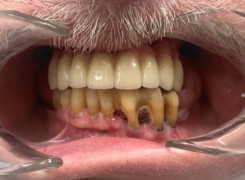

Pan Ryszard trafił do Naszego Gabinetu z jasno sprecyzowanym oczekiwaniem. Miał 84 lata i chciał odzyskać możliwość swobodnego spożywania posiłków oraz poprawienia sobie komfortu życia a także prosił aby przywrócić mu piękny uśmiech jakim cieszył się przed laty. Już na początku pierwszej rozmowy zastrzegł, że interesuje go wyłączenie rozwiązanie uzupełnieniem protetycznym stałym. Nie miał zamiaru użytkować żadnych protez ruchomych. Mając na uwadze powyższe wykonaliśmy Panu Ryszardowi zdjęcie pantomograficzne oraz badanie tomograficzne szczęki i żuchwy na postawie których zapanowywaliśmy Pacjentowi optymalne rozwiązanie – stałe uzupełnienie protetyczne w postaci 28 koron cyrkonowych zamontowanych do dwóch belek cyrkonowych które będą przymocowane do 16 implantów w konfiguracji 8 wszczepów w szczęcie 8 w żuchwie. Po omówieniu powyższego planu przystąpiliśmy do Wspólnej pracy której efekty w poszczególnych etapach prezentujemy poniżej.